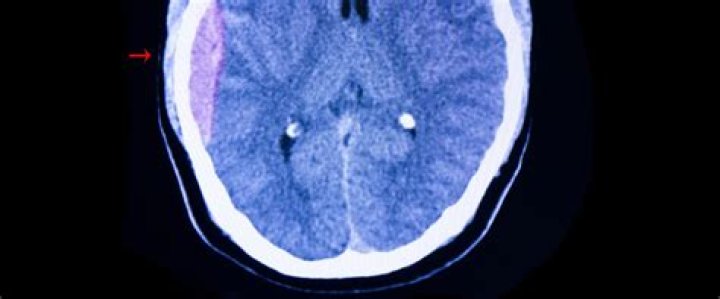

Complications. A severe head injury can result in pressure being placed on the brain because of bleeding, blood clots or a build-up of fluid. This can sometimes lead to brain damage, which can be temporary or permanent.

• Intracranial hematoma (ICH). This is bleeding under the skull in the brain that forms a clot. ...

What is the most common complication of a head injury?

The most common short-term complications associated with TBIs include cognitive impairment, difficulties with sensory processing and communication, immediate seizures, hydrocephalus, cerebrospinal fluid (CSF) leakage, vascular or cranial nerve injuries, tinnitus, organ failure, and polytrauma.